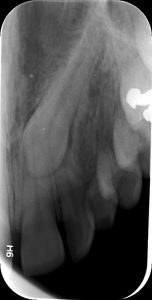

Η οπισθοφατνιακή ακτινογραφία λαμβάνεται με την τοποθέτηση του ακτινογραφικού πλακιδίου εσωτερικά των δοντιών (προς την πλευρά της γλώσσας ή του ουρανίσκου) και παράλληλα με αυτά. Χρησιμοποιείται ειδικός συγκρατητήρας του φιλμ, τον οποίο δαγκώνει ο εξεταζόμενος. Με αυτή απεικονίζονται ένα ή περισσότερα δόντια (τόσο η μύλη, όσο και η ρίζα αυτών), καθώς και τμήμα του φατνιακού οστού που περιβάλλει τις ρίζες των δοντιών. Αποτελεί την πιο απλή οδοντιατρική ακτινογραφική απεικόνιση. Χρησιμοποιούνται τρία μεγέθη φιλμ ή πλακιδίου ανάλογα με την περιοχή που θέλουμε να απεικονιστεί, το μέγεθος του στόματος του εξεταζόμενου και την ηλικία του. Η λήψη της είναι γρήγορη (διαρκεί λίγα δευτερόλεπτα) και ανώδυνη.

Η οπισθοφατνιακή ακτινογραφία μεταξύ άλλων μας επιτρέπει:

• την ανίχνευση οδοντικών τερηδόνων, τον καθορισμό της έκτασης και του βάθους τους και της σχέσης τους με τον πολφό του δοντιού

• τη μελέτη των ριζών των δοντιών (αριθμός, μορφολογία και πιθανή κάμψη αυτών, ύπαρξη απορρόφησης ή κατάγματος)

• τη μελέτη του αριθμού, της μορφολογίας, του εύρους και της πορείας των ριζικών σωλήνων εντός των ριζών

• τη μελέτη των σκληρών ιστών του περιοδοντίου, δηλαδή του φατνιακού οστού που περιβάλλει και στηρίζει το δόντι και του περιοδοντικού συνδέσμου. Σε περίπτωση περιοδοντικής νόσου, καθορίζεται η εντόπιση, ο βαθμός και η φύση (οριζόντια, γωνιώδης) της απορρόφησης του φατνιακού οστού

• τη μελέτη του φατνιακού οστού της περιακρορριζικής περιοχής του δοντιού για ύπαρξη παθολογικών εξεργασιών (απόστημα, κοκκίωμα, κύστη κ.λ.π.)

• την ανίχνευση κατάγματος των δοντιών.